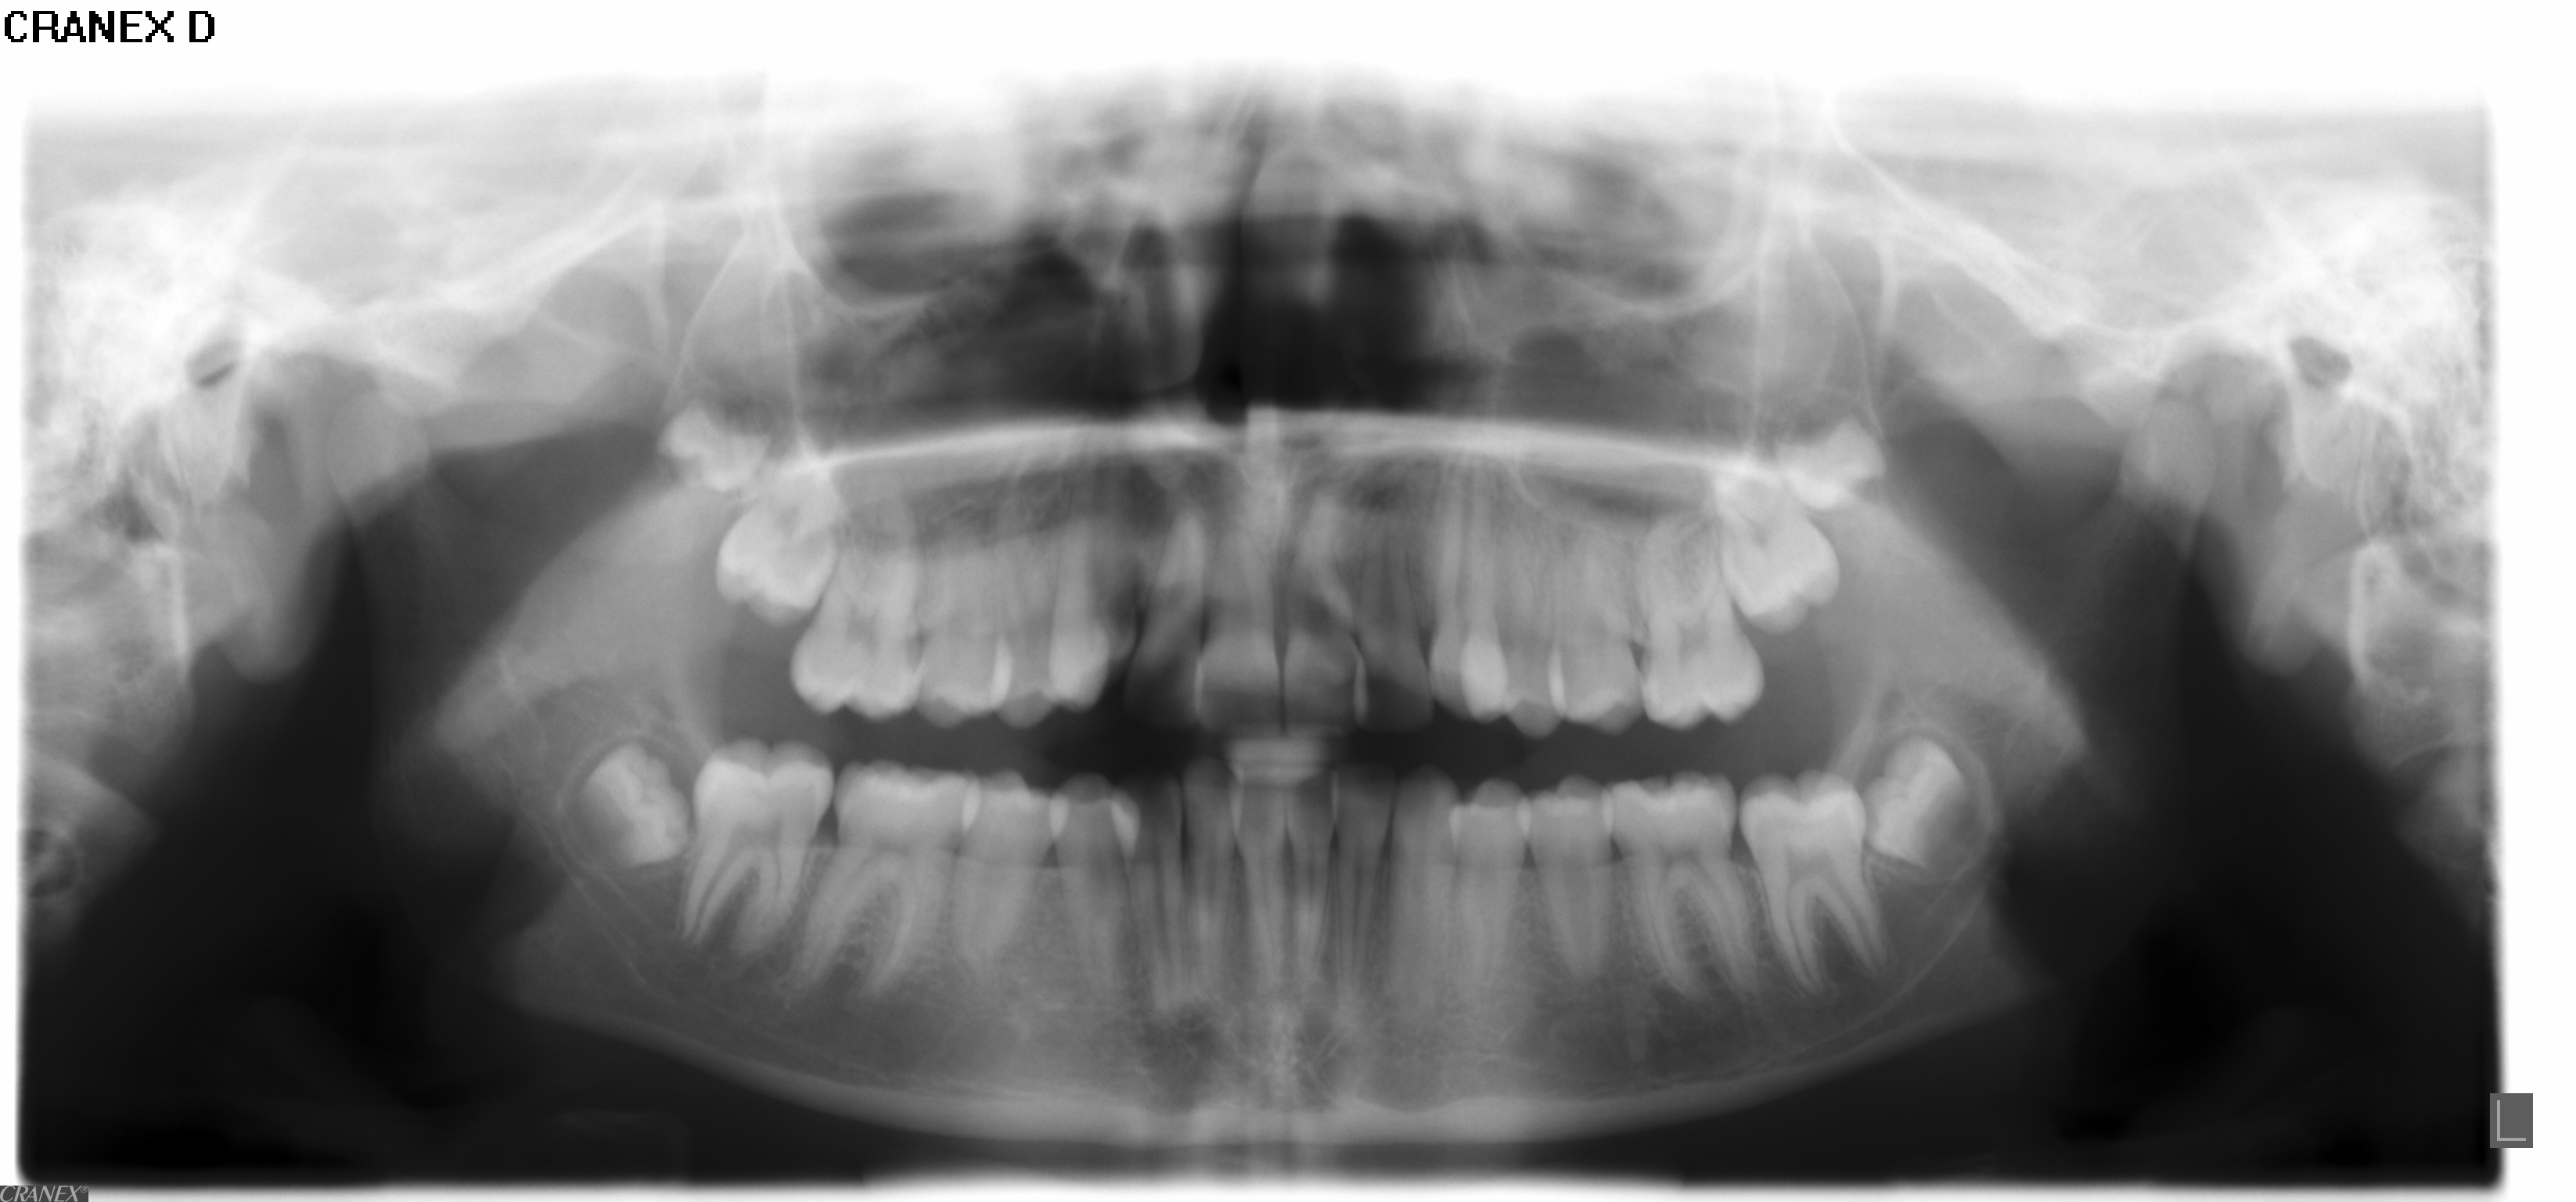

• Panorama viser, om alle tænder er anlagt, og om tandrødder og kæbeled ser normale ud.

• Profilrøntgen giver et billede af, hvordan kæberne er placeret i forhold til hinanden og i forhold til resten af kraniet. Derudover giver det et indtryk af, hvordan væksten vil udfolde sig.

• I nogle tilfælde tages der også et røntgenbillede af hånden, for at se hvor langt dit barn er i sin vækst.

• Der tages røntgenbillede af fortænderne i overkæben som et referencebillede, da disse af og til bliver skadet lidt af en bøjlebehandling. Cirka et halvt år inde i behandlingen bliver der taget ét billede igen som kontrol.

• Alt materiale studeres af en specialtandlæge, der udarbejder en behandlingsplan.